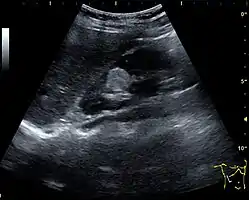

Figure 5. Simple renal cyst with posterior enhancement in an adult kidney. Measurement of kidney length on the US image is illustrated by '+' and a dashed line.[1]